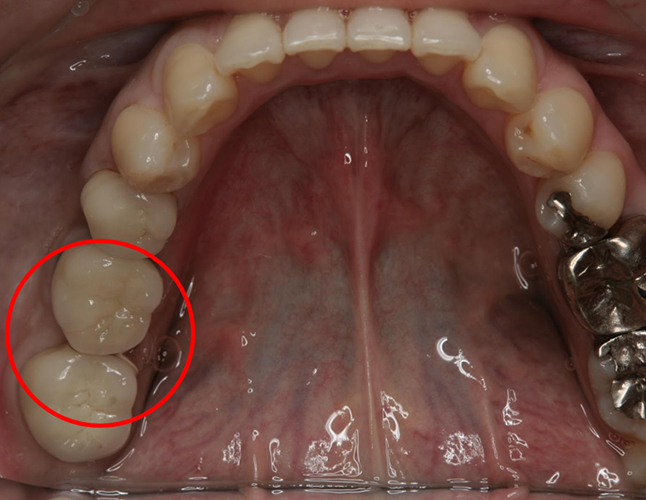

その後、骨にインプラントを埋めて、6週間後に歯型を取りセラミックの歯を作成、更にインプラント部位(赤丸部分)の前後の歯もセラミックで作成し装着しています。

このように、1本や2本だけ歯を失った場合には、最近ではインプラント治療も比較的短期間に終われる場合が多くあります。見た目も自然に仕上げることができますので、お気軽にご相談くださいね。